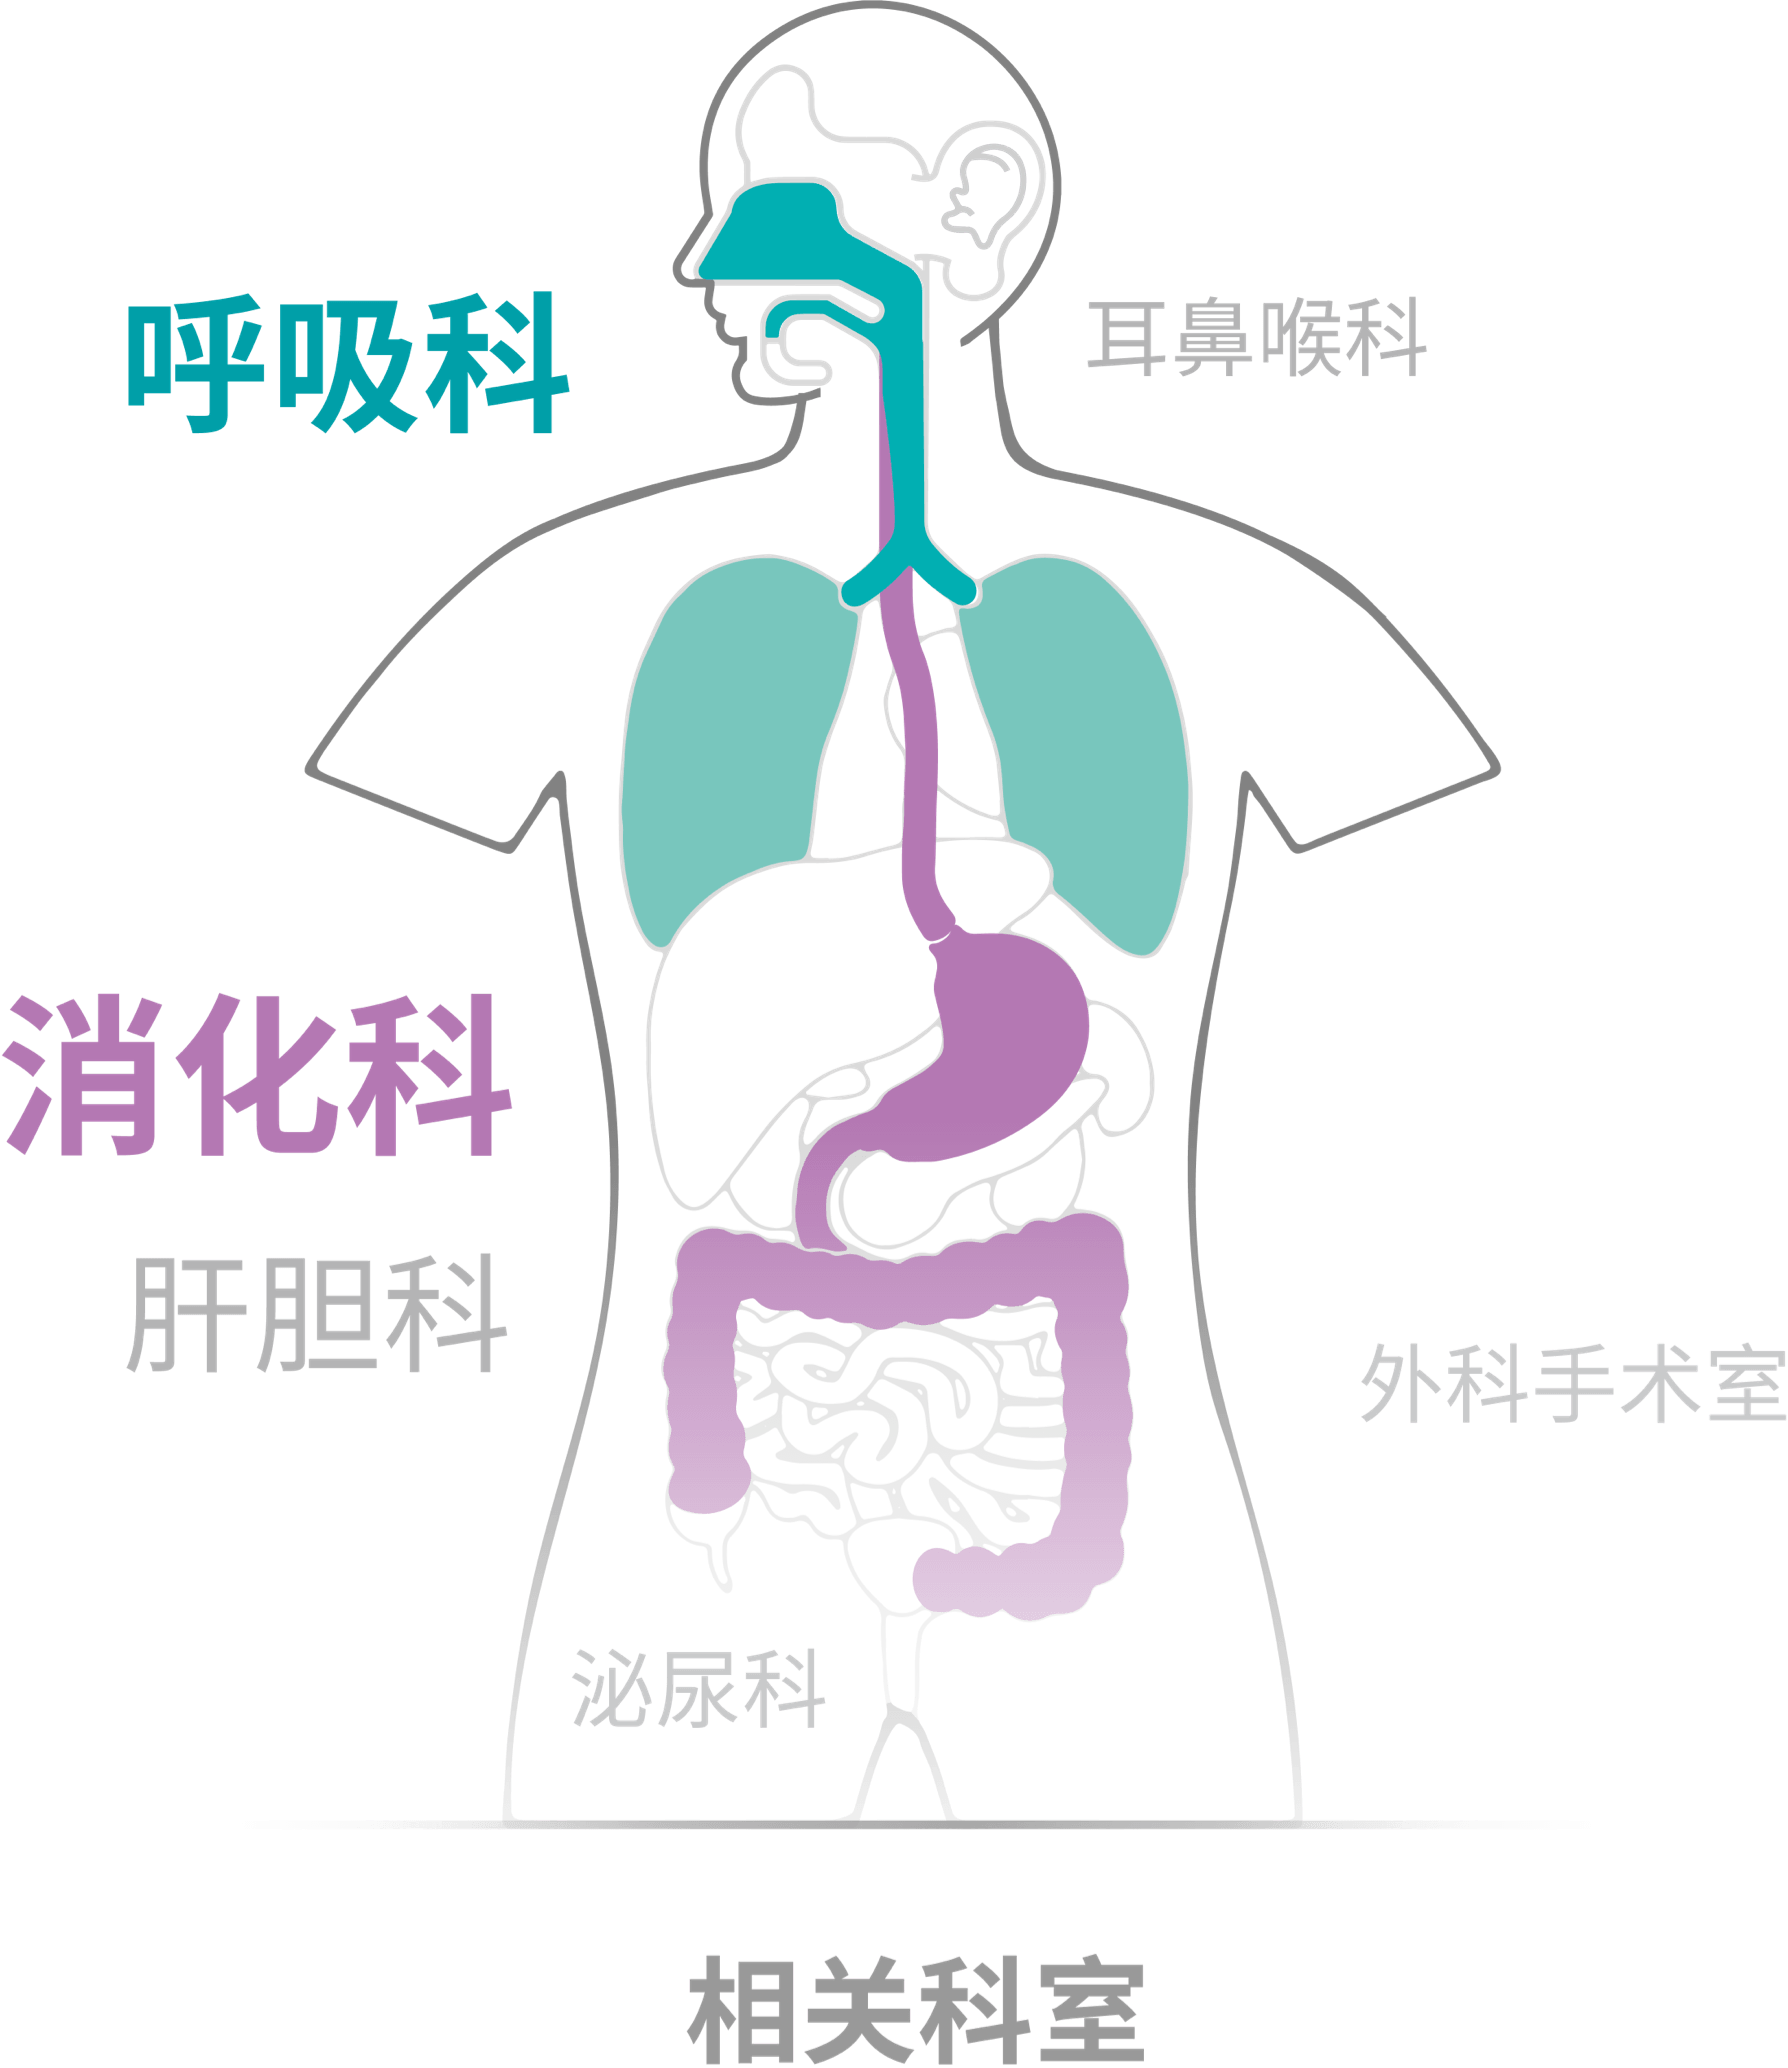

X-2600系列产品为消化呼吸内镜以及硬镜、外科软镜均支持使用的兼容性平台。医生能够根据手术需要快速切换内镜产品,更好地满足临床需求。